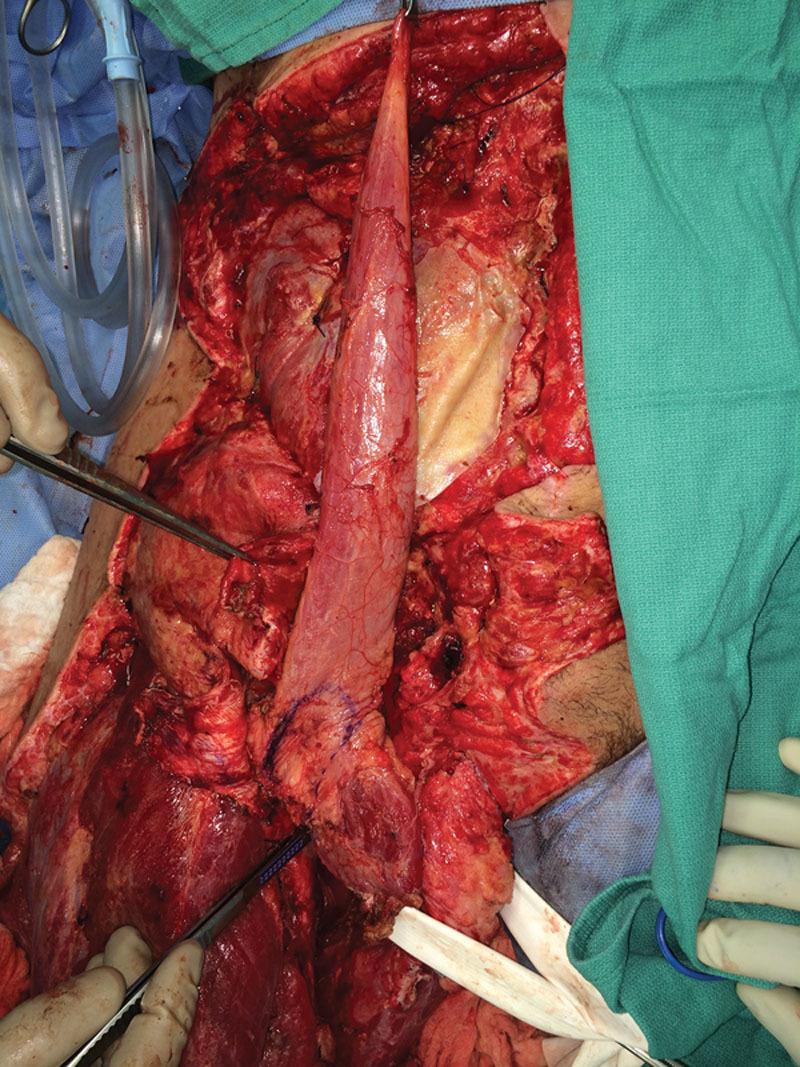

Abdominal wall reconstruction for full-thickness defects is a challenging procedure that usually requires the use of flaps. The gracilis flap is known to be used in hernia repair in which the abdominal muscles are still intact, but there are no reports in literature describing the use of an innervated gracilis for dynamic abdominal wall reconstruction after tissue loss due to severe trauma. We present a surgical technique in which the gracilis is harvested preserving the neurovascular pedicle, then tunneled underneath the adductor longus to cover the lower abdominal defect and provide it with basal muscle tone without tension on the pedicle. This results in restored integrity of the musculofascial abdominal wall and dynamic muscle function and support. The gracilis flap has been proven to be useful and versatile in reconstructive surgery with great potential in abdominal wall reconstruction having minimal donor-site morbidity and hernia recurrence risk.

全层腹壁缺损的腹壁重建是一项具有挑战性的手术,通常需要使用皮瓣。已知股薄肌皮瓣用于腹肌仍完整的疝修补,但文献中没有关于在严重创伤导致组织缺失后使用带神经支配的股薄肌进行动态腹壁重建的报道。我们介绍一种手术技术,即保留神经血管蒂切取股薄肌,然后将其在长收肌下方穿隧,以覆盖下腹部缺损并为其提供基础肌张力,同时使蒂部无张力。这导致腹壁肌筋膜完整性得以恢复以及动态肌肉功能和支撑得以恢复。股薄肌皮瓣已被证明在重建手术中有用且用途广泛,在腹壁重建中具有巨大潜力,供区发病率和疝复发风险极小。